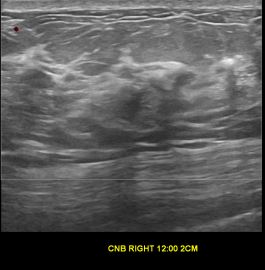

상기환자는 양성추정결절 추적관찰하시는 60대후반 여성분으로 의심스러운 우측혹 조직검사 시행해 유방암으로 진단되었습니다